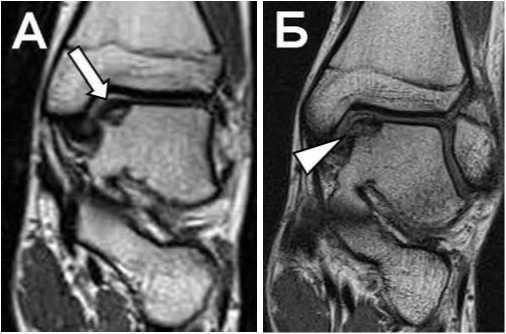

Рис. 8. Т1 TSE Томограммы в коронарной проекции пациента с жалобами на боль в голеностопном суставе без анамнеза острой травмы.

А: В своде блока таранной кости определяется участок формирования костного фрагмента, покрытый суставным хрящом (обычная стрелка).

Б: Тот же пациент, через 1 месяц. Отмечается перелом суставного хряща в Медиальном отделе, нестабильность фрагмента с небольшим смещением (треугольная стрелка).